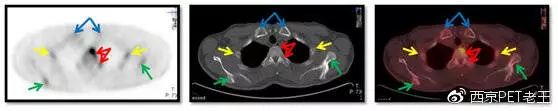

我们又把CT调整到骨窗,看骨骼病变的情况,可以看到全身绝大部分骨骼都有转移,但骨质结构破坏不明显(中列),说明这种是早期的骨转移,如下图:

红色箭头:胸椎及附件转移;黄色:肋骨转移;绿色:肩胛骨转移;蓝色:锁骨胸骨端转移

红色箭头:胸椎转移;黄色:肋骨转移;蓝色:胸骨转移

红色箭头:股骨头转移;绿色:髋臼转移;黄色:耻骨转移